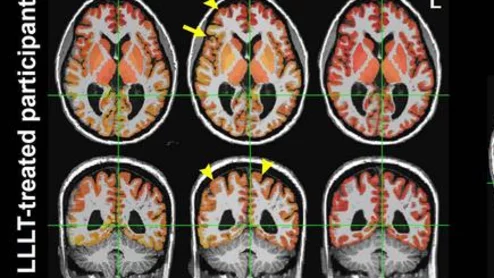

light therapy improves brain connectivity after head trauma

In the study, patients who underwent light therapy showed improved connectivity between seven brain region pairs.